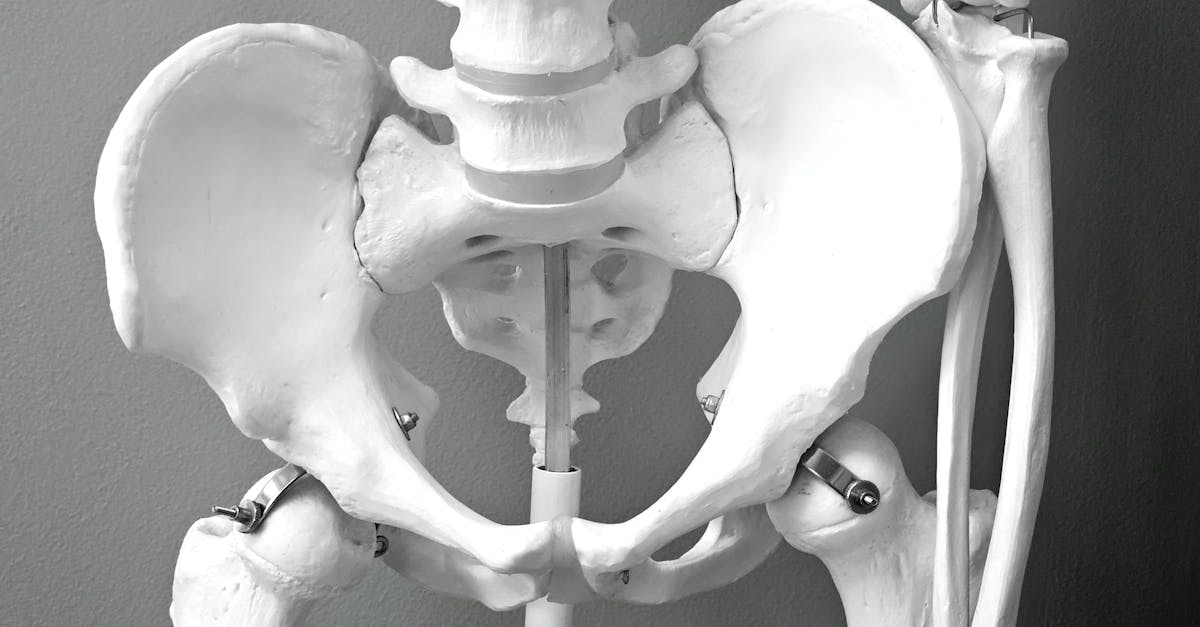

4. Anterior Pelvic Tilt - The Foundation of Lower Body Dysfunction

Anterior pelvic tilt (APT) represents a fundamental postural deviation where the pelvis rotates forward, creating excessive lumbar lordosis and establishing a foundation for numerous lower extremity and spinal pathologies. This condition, characterized by the anterior superior iliac spines positioning lower than the posterior superior iliac spines, affects an estimated 85% of males and 75% of females to varying degrees, making it one of the most common postural abnormalities observed in clinical practice. The biomechanical implications of APT are extensive, as it creates predictable muscle imbalances including tightness in the hip flexors (particularly the iliopsoas), rectus femoris, and lumbar erectors, while simultaneously weakening the gluteus maximus, hamstrings, and deep abdominal muscles. Research utilizing electromyographic analysis has demonstrated that APT significantly alters muscle activation patterns during functional movements, leading to compensatory strategies that increase injury risk and reduce movement efficiency. The condition is strongly associated with lumbar disc herniation, facet joint syndrome, sacroiliac joint dysfunction, and hip impingement due to the altered biomechanics it creates throughout the lumbopelvic region. Clinical studies have shown that individuals with significant APT demonstrate up to 40% reduction in gluteus maximus activation during hip extension activities, contributing to the development of gluteal amnesia and subsequent kinetic chain dysfunction. Furthermore, APT affects gait mechanics, creating increased lumbar extension moments during walking and running, which can accelerate degenerative changes in the lumbar spine. Comprehensive treatment protocols addressing hip flexor flexibility, core stabilization, and posterior chain strengthening have proven highly effective in correcting APT and preventing associated pathologies.